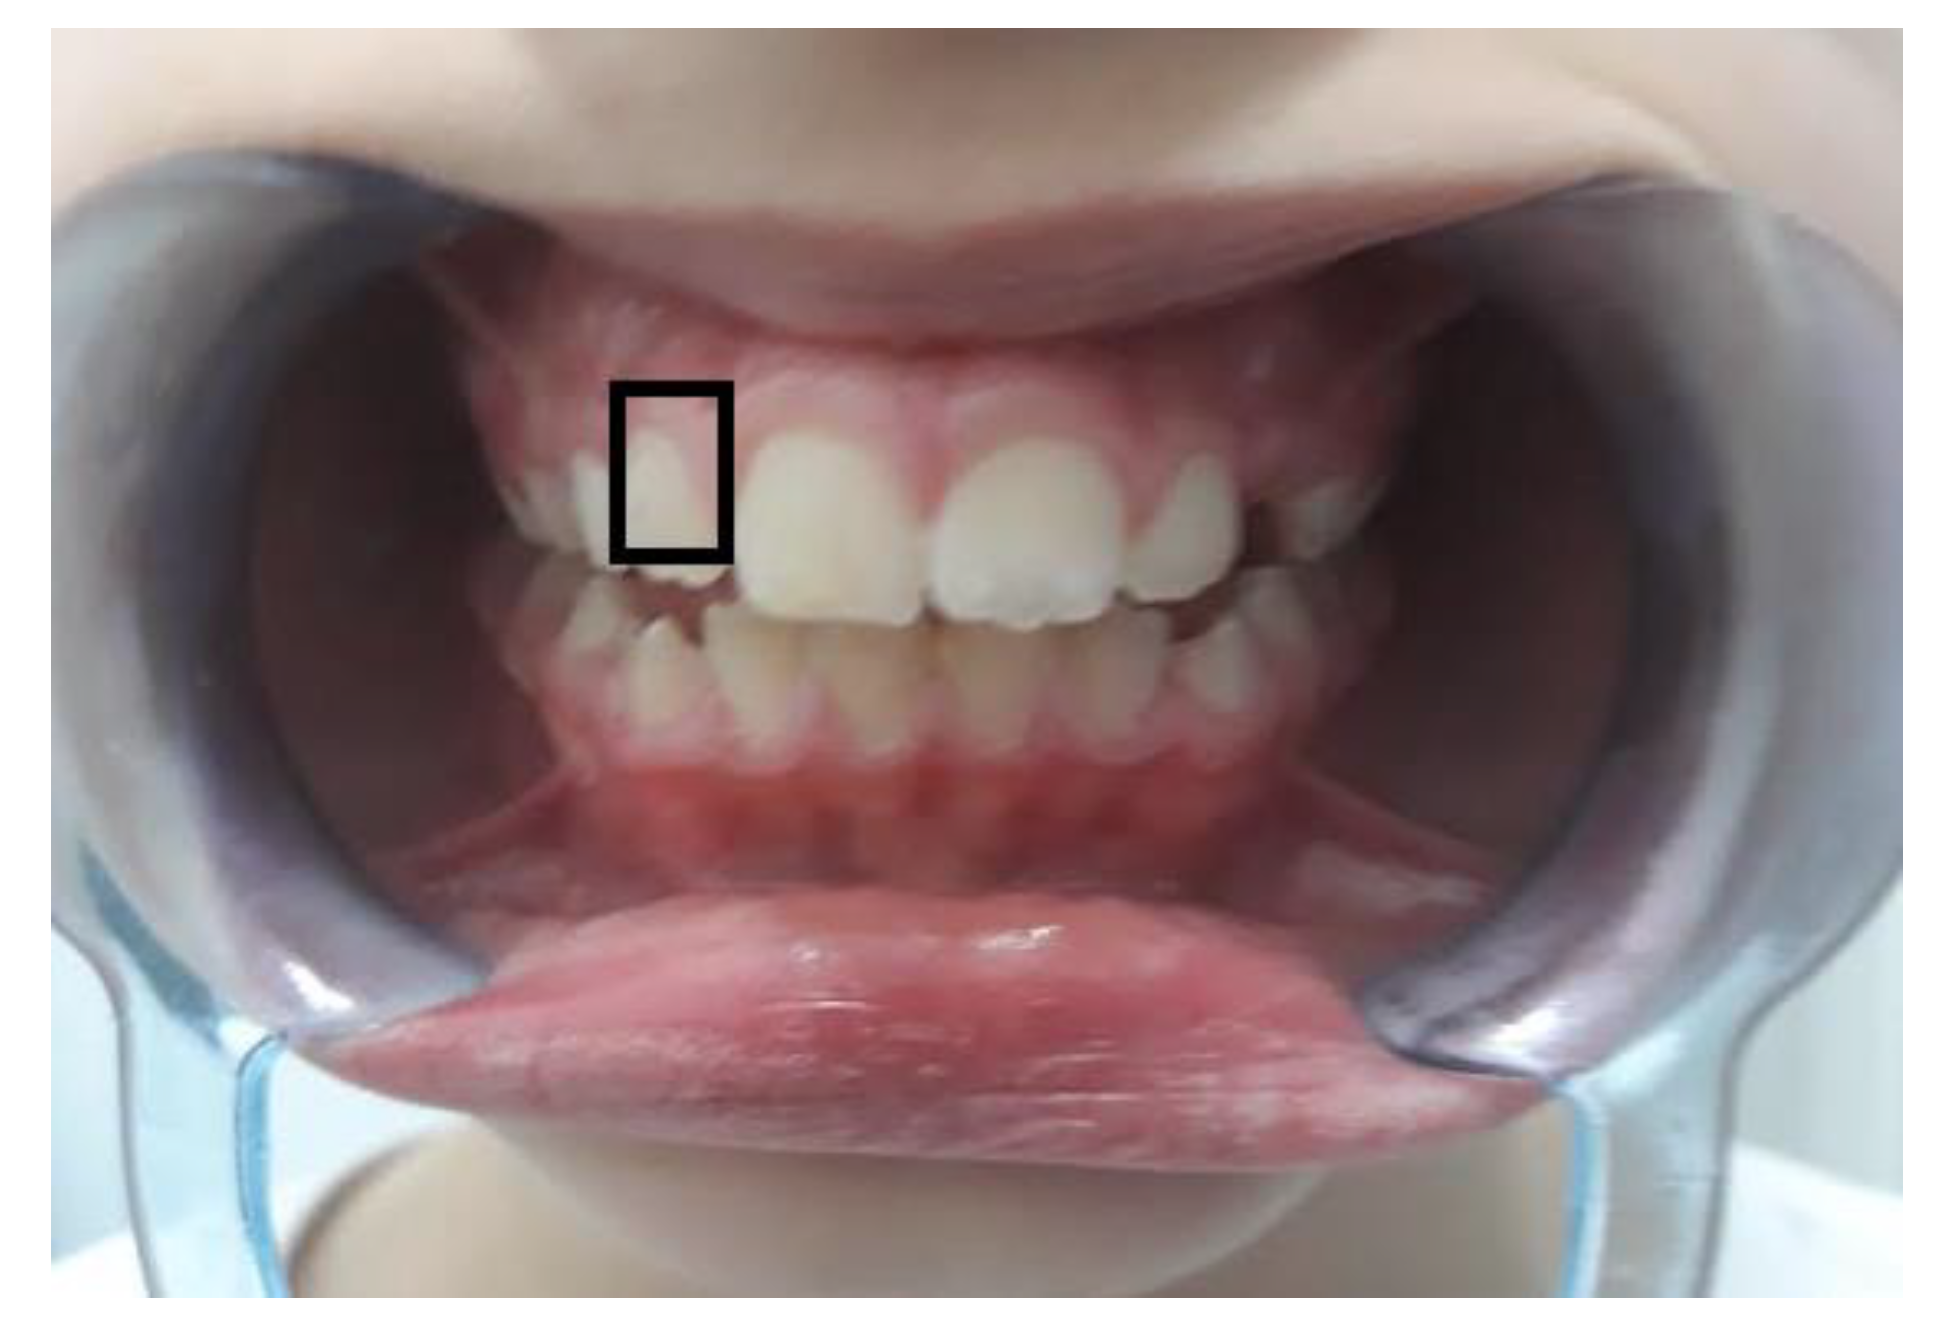

For each of the 190 dental selfies, a dentist marked bounding boxes (see Figure 3) around the eight front-most teeth (see Figure 4 for the notation)—the four central incisors (upper right: 11, upper left: 21, lower left: 31 and lower right: 41) and four lateral incisors (upper right: 12, upper left: 22, lower left: 32 and lower right: 42)—and each bound area was cropped as a separate image. Producing a total dataset of 1520 single tooth (and surrounding gum) images.

Figure 3. A dental selfie (out of the 190 collected). The bounding box marked by the dentist around the upper right lateral incisor (tooth #12) shown outlined in black. (One of eight bounding boxes used to crop single tooth images from the selfie).